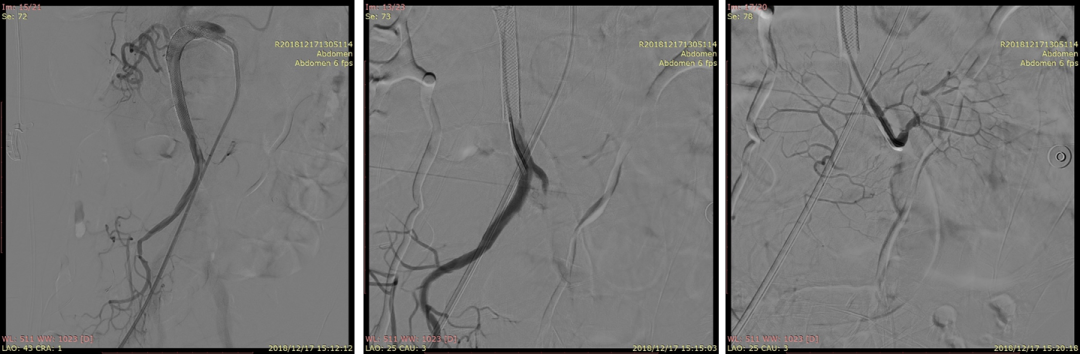

20181223CTA(术后6天)